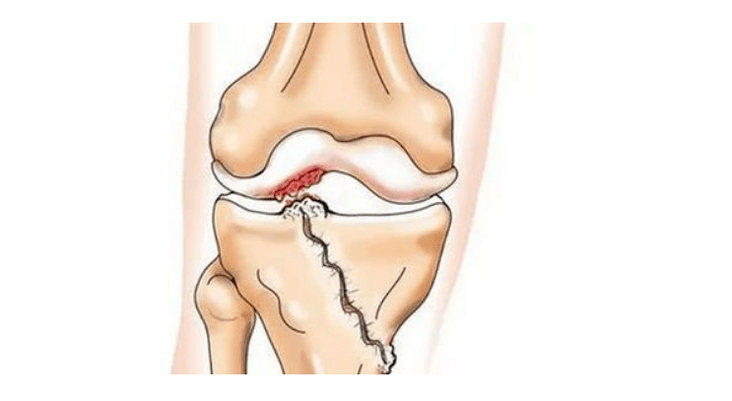

ρωγμή στην άρθρωση του γόνατος

Με την αρθροπάθεια (οστεοάρθρωση), εκτός από την προοδευτική καταστροφή του χόνδρου, την απώλεια της ελαστικότητάς του και τις ιδιότητες απορρόφησης κραδασμών, τα οστά εμπλέκονται σταδιακά στη διαδικασία. Υπό φορτίο, εμφανίζονται αιχμηρές άκρες (εξωστώσεις), οι οποίες λανθασμένα θεωρούνται «αποθέσεις αλατιού» - με την κλασική αρθροπάθεια, δεν εμφανίζεται εναπόθεση αλατιού. Καθώς η αρθροπάθεια εξελίσσεται, συνεχίζει να «τρώει» τον χόνδρο. Στη συνέχεια το οστό παραμορφώνεται, εκεί σχηματίζονται κύστεις, επηρεάζονται όλες οι δομές της άρθρωσης και το πόδι λυγίζει.

• τραυματισμούς (κατάγματα, ρήξεις μηνίσκου και πρόσθιου χιαστού συνδέσμου). Δυστυχώς, σε κάθε άτομο, ανεξαρτήτως ηλικίας, αυτοί οι τραυματισμοί οδηγούν σε υπερβολικό στρες στον χόνδρο. Ένα κάταγμα οποιουδήποτε τμήματος των οστών που καλύπτεται με χόνδρο συνοδεύεται από το σχηματισμό μιας ανομοιομορφίας - ενός "βήματος". Σε αυτήν την περιοχή, κατά την κίνηση, εμφανίζεται τριβή και σχηματίζεται αρθροπάθεια.